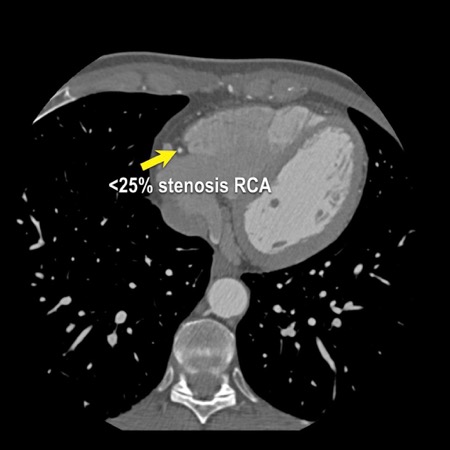

case 1 – CAD-RADS 2/P1

First, scroll through the scan.

Not all images are included. Some images without any abnormalities are skipped

from the series.

How would you describe the findings on the coronary CTA?

The findings are:

- Agatston score of

this patient was 14 (P1). Please, also note the calcification of the aortic valve. - Some partially

calcified and calcified plaques are present in the LAD with mild stenosis

(25-49%). - Calcified-plaque in

the LCX causing minimal stenosis (<25%). - Non-calcified

plaque in the distal RCA causing minimal stenosis (<25%). - This patient classifies

as CAD-RADS 2/P1, which means no further workup is needed.